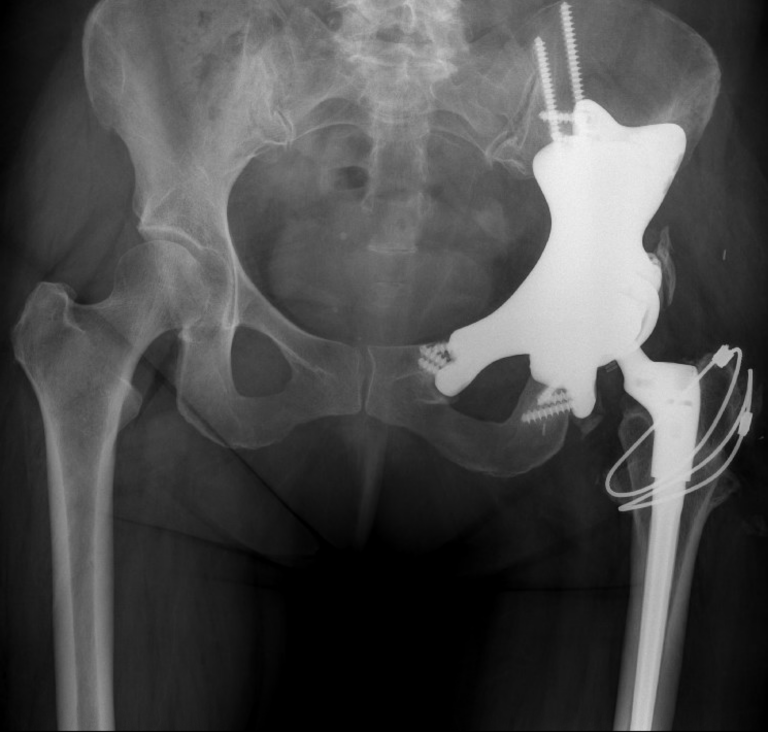

L’implant pelvien 3D est conçu sur mesure à partir d’images obtenues par IRM, tomodensitométrie et d’autres examens d’imagerie. Il est recouvert d’une couche d’argent afin de réduire le risque d’infection, qui est associé à ce type d’intervention.

L’opération, d’une durée de 16 heures, était prévue pour février 2024. Une fois la tumeur retirée, l’équipe chirurgicale a mis en place l’implant. « La conception comprend des guides pour s’assurer que la prothèse s’ajuste parfaitement — et celle de Tracy s’adaptait à son os avec une précision remarquable. Elle a permis de reconstruire la partie du bassin retirée, et Tracy a maintenant une hanche artificielle plutôt qu’un vide à cet endroit », explique le Dr Werier.

L’implant est fabriqué à partir d’un métal poreux qui, au fil de plus de douze mois, permet à l’os avoisinant de croître à l’intérieur de la structure, offrant ainsi à la patiente un bassin solide.